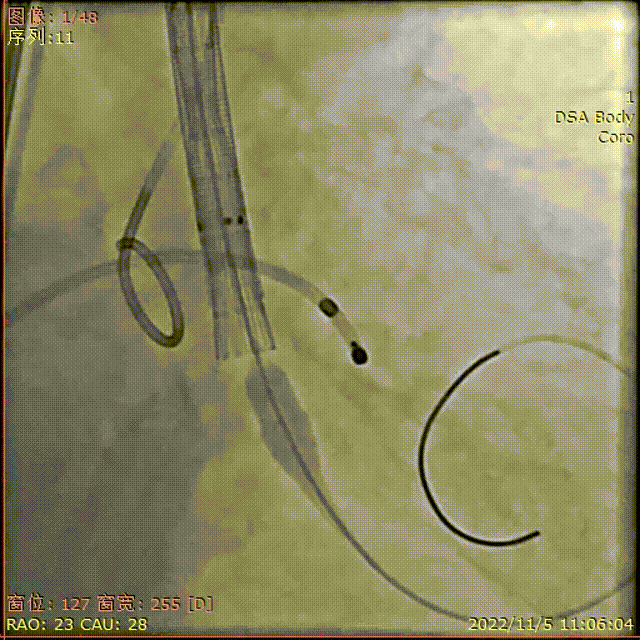

术中影像

主动脉根部造影

导丝顺利跨瓣

TaurusElite输送器顺利过弓

瓣膜初始定位

瓣膜稳定释放到工作位,无位移

工作位多角度评估

瓣膜完全释放